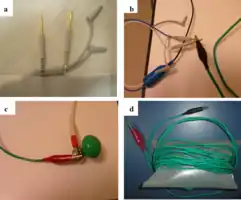

- Connect the device to the energy generator and turn the generator on.[3] The positive electrode goes into the positive connector terminal and the negative electrode goes in the negative connector terminal.[2]

The device inappropriately passing into the inferior vena cava Setup for doing an ECG off the device

Setup for doing an ECG off the device Example of ECG off the device a) free floating in the RV b) in contact with the RV wall